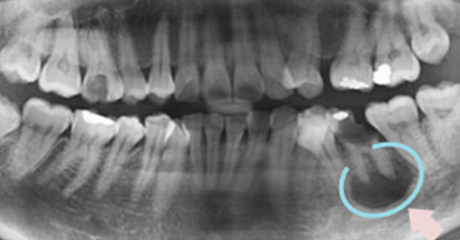

뿌리가 곪으면서 턱뼈 내부에 농 주머니가 생기게 됩니다.